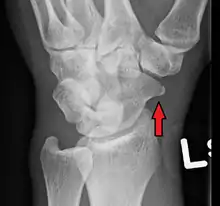

| An X-ray showing a fracture through the waist of the scaphoid | |

A subtle scaphoid fracture